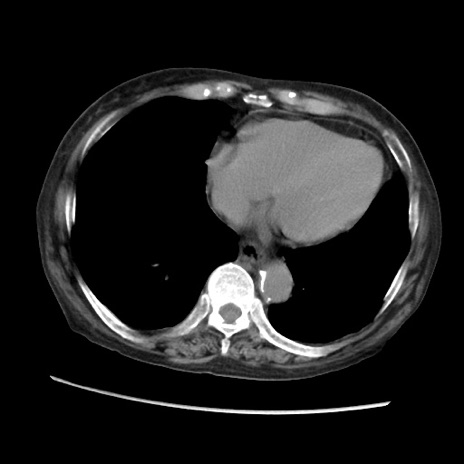

矢状断像